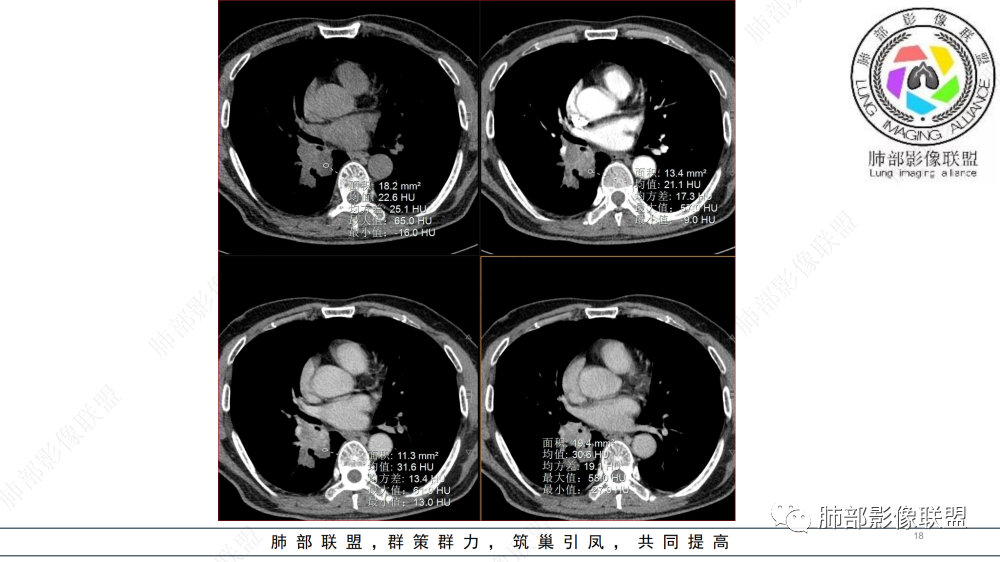

中老年男性,右肺下叶背段支气管内新生物,近端可见息肉样突起,远端沿分支支气管生长堵塞,肺门口病灶增强后明显强化,峰值达140hu,远端部分强化不明显考虑粘液栓,考虑典型类癌,鉴别鳞癌。